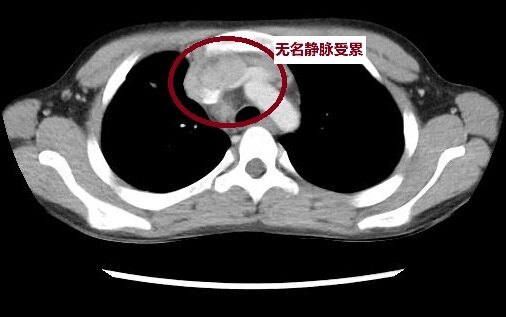

病例簡(jiǎn)介:患兒,男,12歲,腹痛行闌尾手術(shù)時(shí)發(fā)現(xiàn)前縱隔占位,外院手術(shù)部分切除,病理提示淋巴上皮癌,外院予以FLP化療,四療后復(fù)查前縱隔占位,多發(fā)淋巴結(jié)腫大,遂之我院。多學(xué)科會(huì)診后,建議手術(shù)切除殘留病灶,腫瘤科化療放療同步,必要時(shí)免疫治療。術(shù)中見(jiàn)腫瘤累計(jì)無(wú)名靜脈及肺靜脈,術(shù)中經(jīng)心包內(nèi)游離肺靜脈,切除部分受累無(wú)名靜脈后行無(wú)名靜脈成型,腫瘤肉眼完整切除。術(shù)后病理證實(shí)為胸腺淋巴上皮瘤樣癌,術(shù)后予以TP方案化療及放療,目前處理完全緩解階段。?胸腺淋巴上皮瘤樣癌(LELC):是兒童時(shí)期極罕見(jiàn)的惡性腫瘤,至今全球報(bào)道兒童病例數(shù)不超過(guò)20例,臨床表現(xiàn)多樣,少數(shù)患者無(wú)明顯臨床癥狀,早期診斷困難,復(fù)發(fā)率高,生存期短,預(yù)后極差。它是一種原發(fā)性胸腺癌,具有未分化癌細(xì)胞合體性生長(zhǎng)特征,伴有類(lèi)似鼻咽部未分化癌的淋巴漿細(xì)胞浸潤(rùn)。有報(bào)道胸腺LELC與EB病毒(EBV)感染可能有關(guān),但未有進(jìn)一步證實(shí)。?【流行病學(xué)】通常男性病人是女性的2倍多。病人的年齡范圍4~76歲,中間年齡41歲,發(fā)病雙峰年齡分別為14歲和48歲。?【發(fā)生部位】胸腺LELC發(fā)生在前縱隔,診斷時(shí)可侵犯鄰近器官,如淋巴結(jié)、肺、血管,亦可發(fā)生遠(yuǎn)處轉(zhuǎn)移,如肝和骨是常見(jiàn)轉(zhuǎn)移部位。?【臨床特點(diǎn)】發(fā)病隱匿,早期無(wú)癥狀,偶然經(jīng)影像學(xué)檢查發(fā)現(xiàn)前縱隔包塊;進(jìn)展快,病人通常訴胸痛、咳嗽、呼吸困難等癥狀。多數(shù)晚期病人有上腔靜脈綜合征。不伴有重癥肌無(wú)力或其他圍腫瘤期綜合征,但在兒童有肥大性肺骨關(guān)節(jié)病的報(bào)道。?【治療】胸腺LELC相對(duì)罕見(jiàn),無(wú)統(tǒng)一診療指南。通常LELC的治療需要手術(shù)、化療、放療及免疫等綜合治療。不少患兒確診時(shí)多數(shù)已發(fā)生轉(zhuǎn)移或累計(jì)周?chē)M織,尤其是肺門(mén),無(wú)法一期手術(shù),建議先行新輔助化療,如TP方案。2-4療程影像學(xué)評(píng)估手術(shù)條件。手術(shù)治療:LELC惡性度較高,多數(shù)累計(jì)周?chē)?,故一般建議正中開(kāi)胸手術(shù),術(shù)中精細(xì)操作,盡可能擴(kuò)大切除。極少數(shù)早期患者可行胸腔鏡輔助下前縱隔腫瘤切除術(shù)。放療:目前認(rèn)為放療可顯著降低LELC復(fù)發(fā),延長(zhǎng)患者預(yù)后。部分腫瘤巨大不具備手術(shù)條件的患兒可行術(shù)前放療。免疫治療:目前尚無(wú)指南,有病例報(bào)道提示以PDL1抗體治療后可顯著改善患兒癥狀。?【預(yù)后】胸腺LELC是一種高度惡性腫瘤,預(yù)后差。EBV存在與否似乎無(wú)預(yù)后意義。但隨著新治療方法的應(yīng)用,有望顯著提高胸腺LELC患兒預(yù)后??偨Y(jié)我中心病例,2016年至今,我院已接診10名胸腺LELC患兒,年齡在9-15歲之間,中位年齡13歲,男性7例,女性3例。經(jīng)過(guò)我院兒外科、兒童腫瘤科、放療科,有效緩解率為60%(6例患兒緩解),近年P(guān)DL1抗體的使用,使胸腺LELC患兒預(yù)后有了顯著的改善。如何聯(lián)系我們:上海交通大學(xué)醫(yī)學(xué)院附屬新華醫(yī)院小兒普外科/兒腫瘤外科,聯(lián)系方式如下:周一上午專(zhuān)家門(mén)診,周四下午特需門(mén)診(新華醫(yī)院28號(hào)樓4樓);新華兒童腫瘤外科住院病房(新華醫(yī)院27號(hào)樓六樓)直接聯(lián)系武志祥副主任醫(yī)師(好大夫)本文僅代表一般情況及科普目的,具體個(gè)體需充分了解病情及相關(guān)檢查情況下做出相符合的專(zhuān)業(yè)處理意見(jiàn),謝謝!